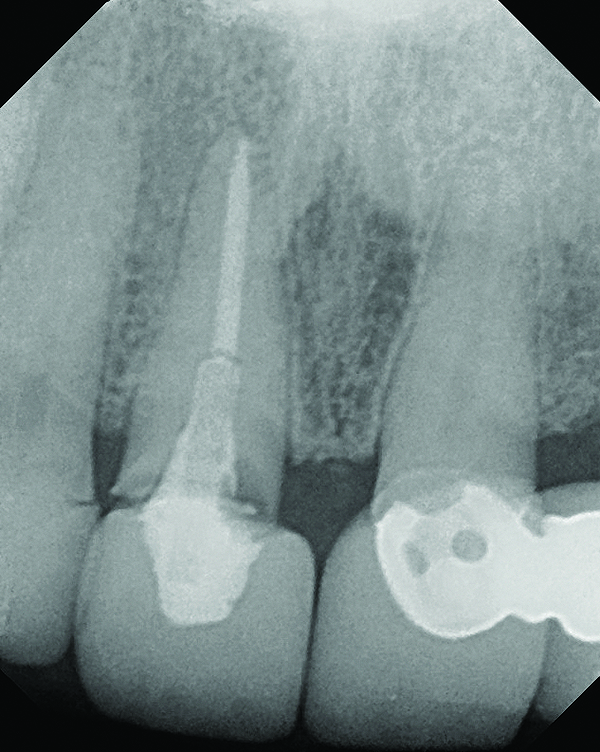

Fig 18. Radiograph taken immediately after placement of the definitive crown confirmed complete removal of all the cement.

Figure 18

The crown was inserted and secured with a luting composite (Multilink® Automix, Ivoclar Vivadent) (Figure 17); a radiograph confirmed complete removal of excess cement (Figure 18). At the 4-month follow-up appointment, the soft tissues were healed within normal limits, and the patient was pleased with the esthetic outcome of the definitive restoration (Figure 19 and Figure 20).